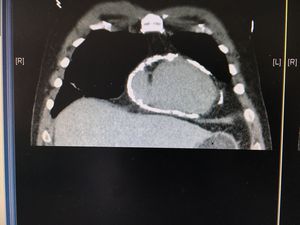

What do you guys think?

Pericaditis constrictiva